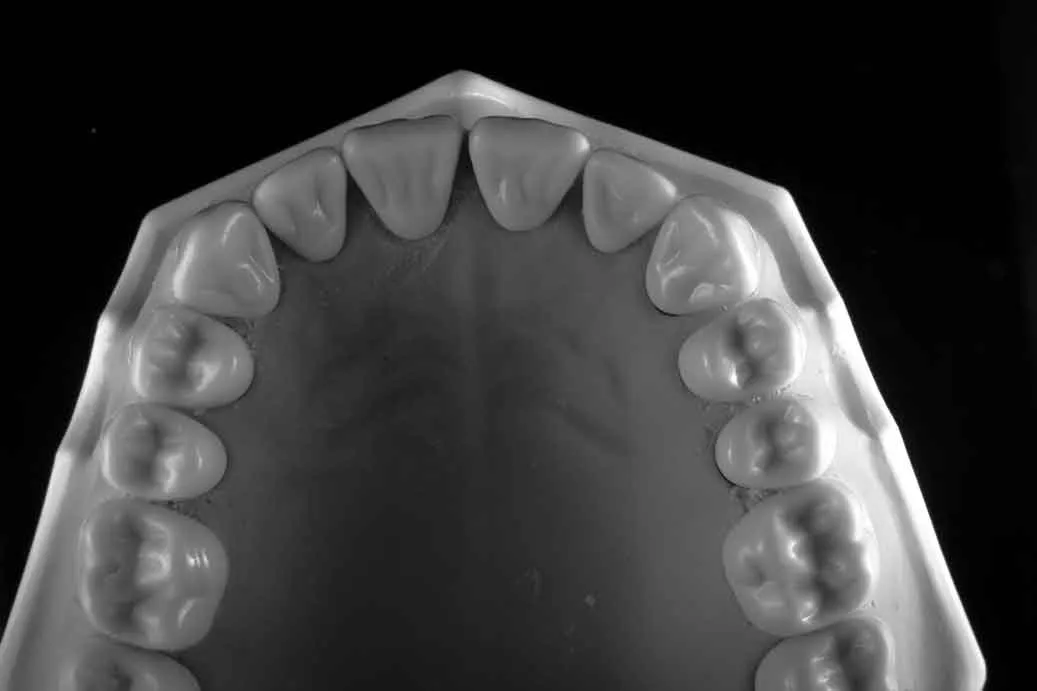

Caso clinico: espansione crestale ERE con impianto immediato e rigenerazione simultanea. Da ponte fallito a impianto in un'unica seduta.

La tecnica split crest espande le creste sottili per consentire il posizionamento implantare. Indicazioni, strumentazione e risultati clinici.

Bonebenders: espansione osteo-mucosa naturale per impianti. 100% osso e mucosa cheratinizzata senza biomateriali. Caso clinico e risultati straordinari.